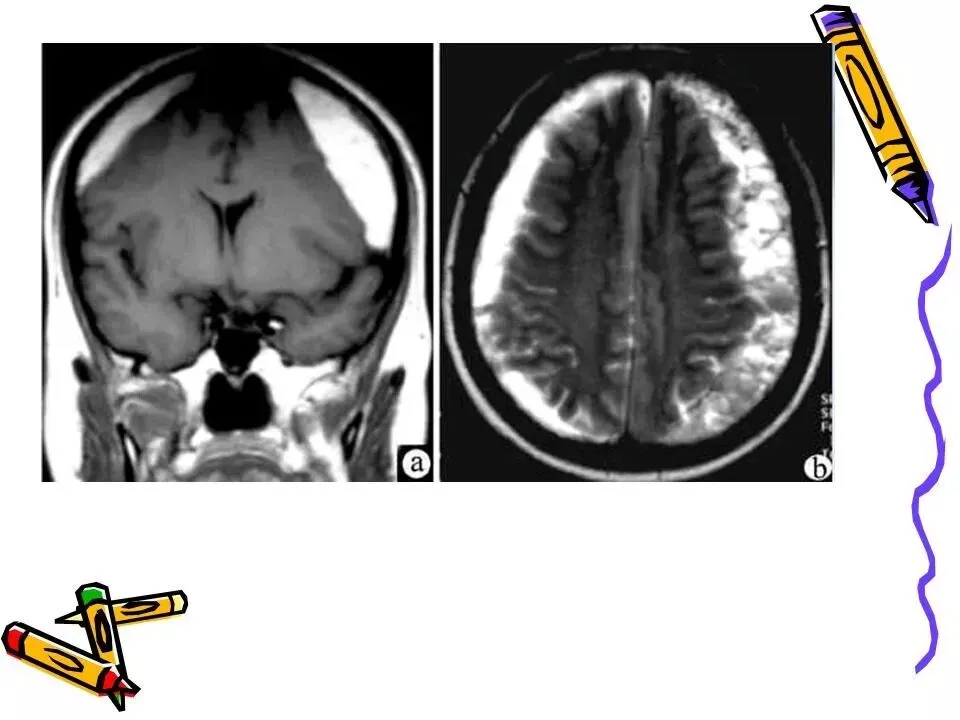

>常见颅脑外伤CT诊断(PPT)

常见颅脑外伤CT诊断(PPT)